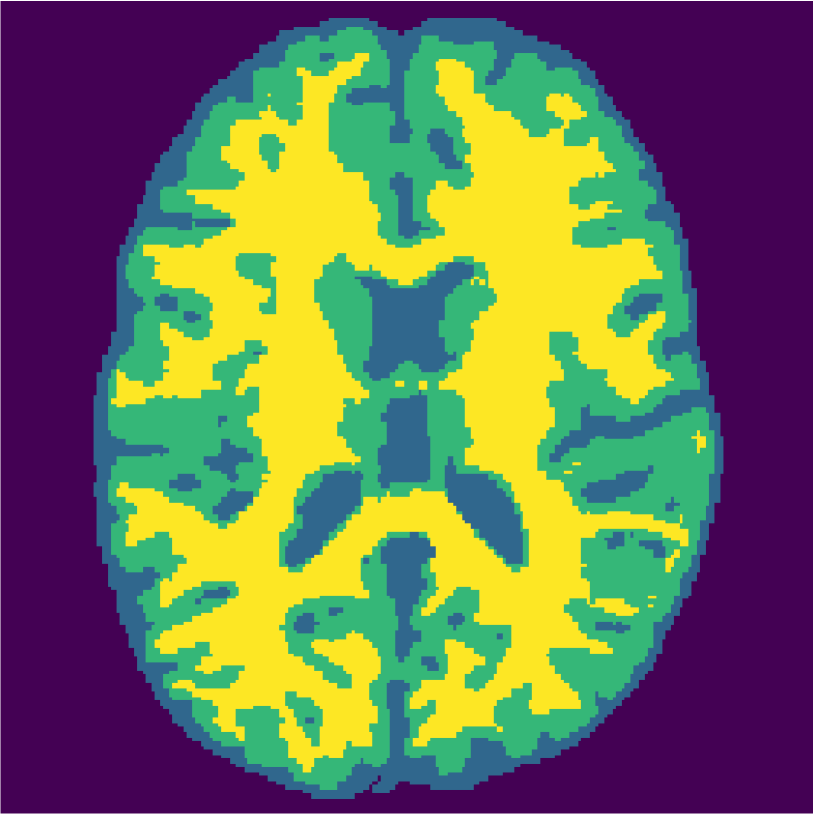

Examples of the segmentation results on one of the target test images are shown in Figure 8 for experiment 2.1, Figure 9 for experiment 2.2, and Figure 10 for experiment 2.3. Examples are shown after using 1 target patch per tissue for training, and after using 100 target patches per tissue for training. The results show that only the mrai-net classifier is able to predict a segmentation that approaches the ground truth with only 1 target patch per tissue for training (error for experiment 2.1 = 0.269, experiment 2.2 = 0.403, experiment 2.3 = 0.320), while the source and target classifiers cannot (source error for experiment 2.1 = 0.667, experiment 2.2 = 0.653, experiment 2.3 = 0.435; target error for experiment 2.1: 0.591, experiment 2.2: 0.614, experiment 2.3 = 0.596). After using 100 patches the source and target classifiers can predict a gross segmentation of WM, GM and CSF (source error for experiment 2.1 = 0.213, experiment 2.2 = 0.384, experiment 2.3 = 0.363; target error for experiment 2.1: 0.205, experiment 2.2: 0.368, experiment 2.3 = 0.368), but the mrai-net classifier prediction shows more details and a lower tissue classification error (error for experiment 2.1 = 0.111, experiment 2.2 = 0.276, experiment 2.3 = 0.284).

Appendix A describes the nuclear magnetic resonance (NMR) relaxation times for the tissues in the Brainweb anatomical models, for 1.5 and 3.0 Tesla field strengths. The tissues in the anatomical models are grouped into ”background” (BKG), ”cerebrospinal fluid” (CSF), ”gray matter” (GM), and ”white matter” (WM) to compose the ground truth segmentation labels for the simulated scans. The simulations result in images of 256 by 256 pixels, with a 1.0x1.0mm resolution. Figures 5(a) and 5(b) show examples of the Brainweb1.5T and Brainweb3.0T scan of the same subject. For all scans, we used a brain mask to strip the skull.

In order to test the proposed method on real data, we use the publicly available training data (5 subjects) from the MRBrainS challenge444http://mrbrains13.isi.uu.nl/Figure. The acquisition parameters used for simulating the Brainweb3.0T are based on the MRBrainS acquisition protocol (3.0T scanner, gradient-echo, B0 = 3.0T, = flip angle, TE = 4.5ms, and TR = 7.9ms). Figure 5(c) shows an example of an MRBrainS scan. Again, a brain mask is used to strip the skull.